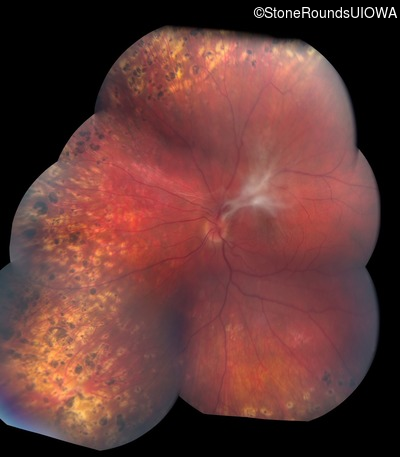

Fundus Montage - Left - 20/60 -1 sc

Exemplar